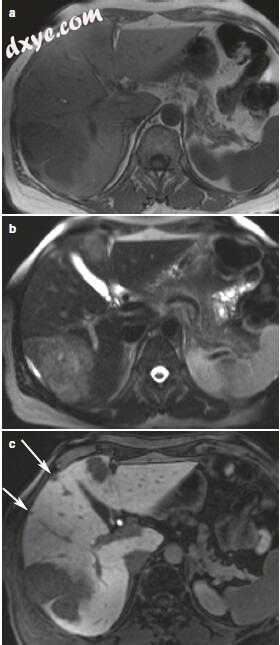

3.jpg

图17.3血管瘤类型1.肝脏特异性MR造影剂。 一名45岁女性,右肝叶有病变(箭头)。 这表现为(a)T2加权成像的高信号强度和(b)T1加权成像的低信号强度和(c-e)显示

4.jpg

图17.4血管瘤3型:非特异性钆螯合物。 (a-c)(a)动脉和(b)门静脉和(c)延迟期的T1加权动态增强T1加权GRE显示结节周边

5.jpg

图17.5血管瘤3型:肝脏特异性MR造影剂。 (a)T2加权TSE显示非常高信号强度的大分叶状病变。 (b-d)动态钆喷酸增强成像显示动脉(b)和静脉期(c)的外周结节增强。在肝胆相(d)中,由于病变中缺乏肝细胞摄取和周围肝实质图像的增强,病变具有显着的低信号。由于动脉血管供应突出,FNH在对比增强CT / MR成像的动脉期显示出明显的均匀增强,其在门静脉期对肝实质迅速变为等密度/等信号。由于其血管成分,中央瘢痕经常表现出延迟增强(图17.6)。另一个关键特征是除了瘢痕之外,与纤维层状HCC中遇到的异质外观相比,FNH通常在外观上是均匀的。